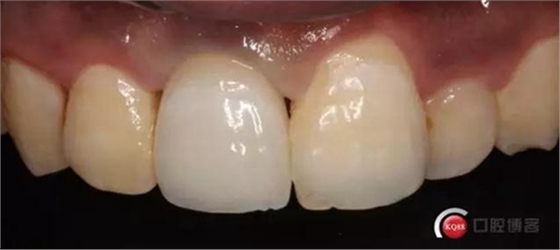

兩個(gè)月后

兩月后牙齦恢復(fù)正常穩(wěn)定。正式取模,E.max鑄瓷修復(fù)

可以看出牙齦袖口很漂亮,修復(fù)體外形也不錯(cuò),就是顏色偏白一點(diǎn),讓患者改色,患者覺得已經(jīng)很滿意了,而且考慮其他牙以后做美白,所以不換了。

可以看出修復(fù)體的邊緣密合度都很好。希望這次修復(fù)能夠讓這顆牙多服役幾年吧